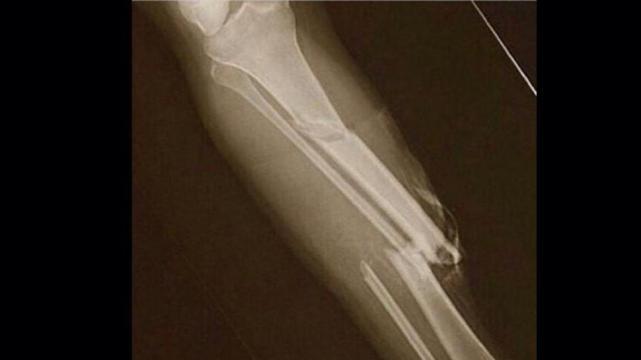

1. fracturas

LESIONES DEPORTIVAS MAS COMUNES

1. Las lesiones eportivas, como su nombre lo indica son lesiones que ocurren en el desarollo de algun deporte o actividad fisca. Son producidas por un mal entrenamiento, calentamiento o porque son accidentales